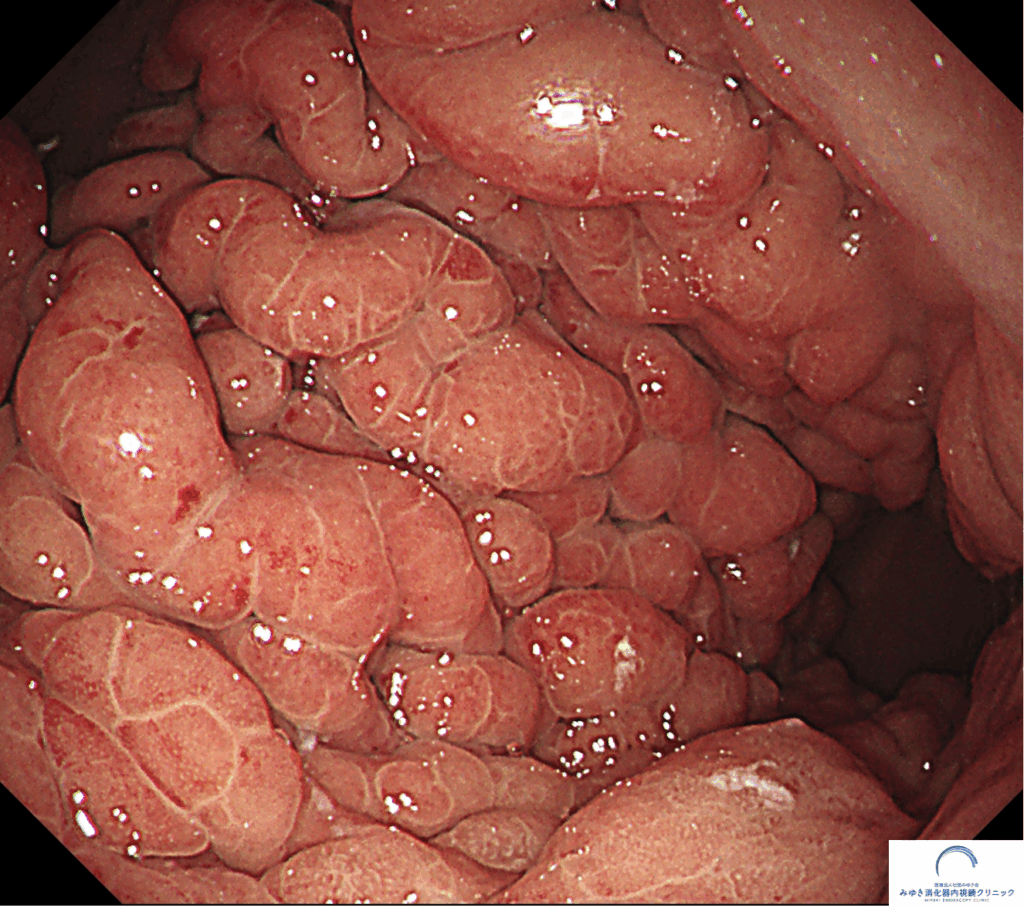

すると、胃のひだが芋虫のように太くなり、空気を入れても胃が膨らまないという異常がみられました。

*参考までに正常な胃の写真です。ひだの太さと胃の広がり方が違うのが一目瞭然です。